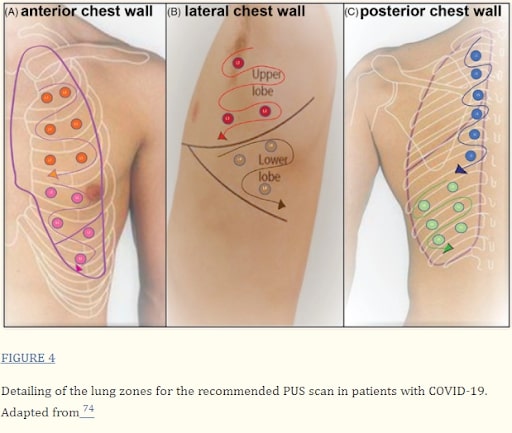

A recent paper in the Journal of Clinical Ultrasound in 2022 summarized various sonographic findings of COVID in the lungs and other organs. The findings also encompass methods for conducting a sonographic examination of the lungs (see below). Other studies have shown that these findings can reflect both the duration of infection and the severity of the disease. Another recent systematic review and meta-analysis demonstrated that the findings of COVID-19 interstitial pneumonia on ultrasound have high diagnostic agreement with CT scans. It can be considered an equally accurate alternative to CT in situations where molecular tests are not available.